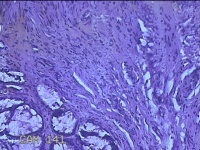

性别

男

年龄

40岁

临床诊断

混合痔

一般病史

反复肛门肿物突出15年。

标本名称

肛门肿物

大体所见

灰白暗红色肿物0.7x0.5x0.2cm一个,表面糜烂。

脱水、透明,浸蜡、脱蜡效果不佳,制片质量差。